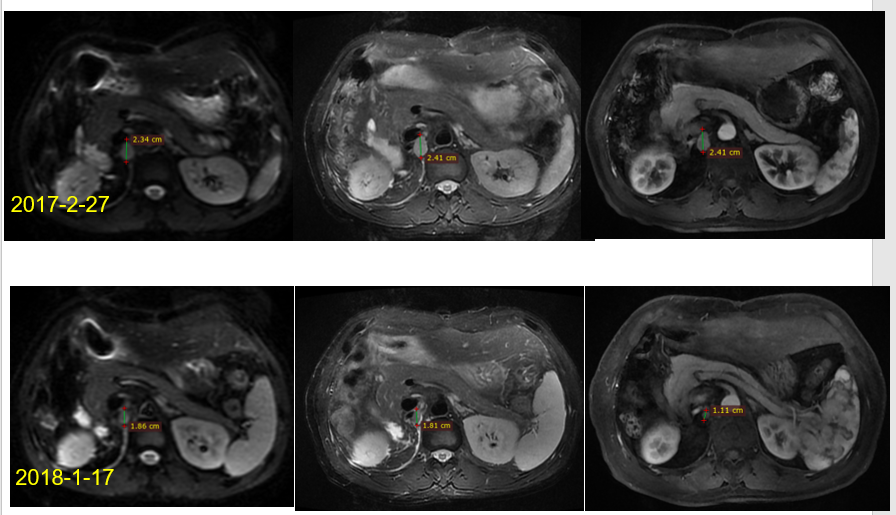

2017年7月再次出现梗阻性黄疸,影像学提示吻合口复发,腹膜后淋巴结转移。予PTCD(经皮肝穿刺胆管引流)下金属支架植入,术后给以信迪利单抗200mg q3w,共9周期。期间CA199直线下降(图2),影像学可评估的后腹膜淋巴结逐渐缩小,失去活性,疗效评价持续完全缓解(CR;图3,图4)。

图3. 信迪利单抗治疗5个月后,与治疗前影像学比较

图4. 信迪利单抗治疗26个月后,于2019年12月复查结果:持续无瘤状态(NED)